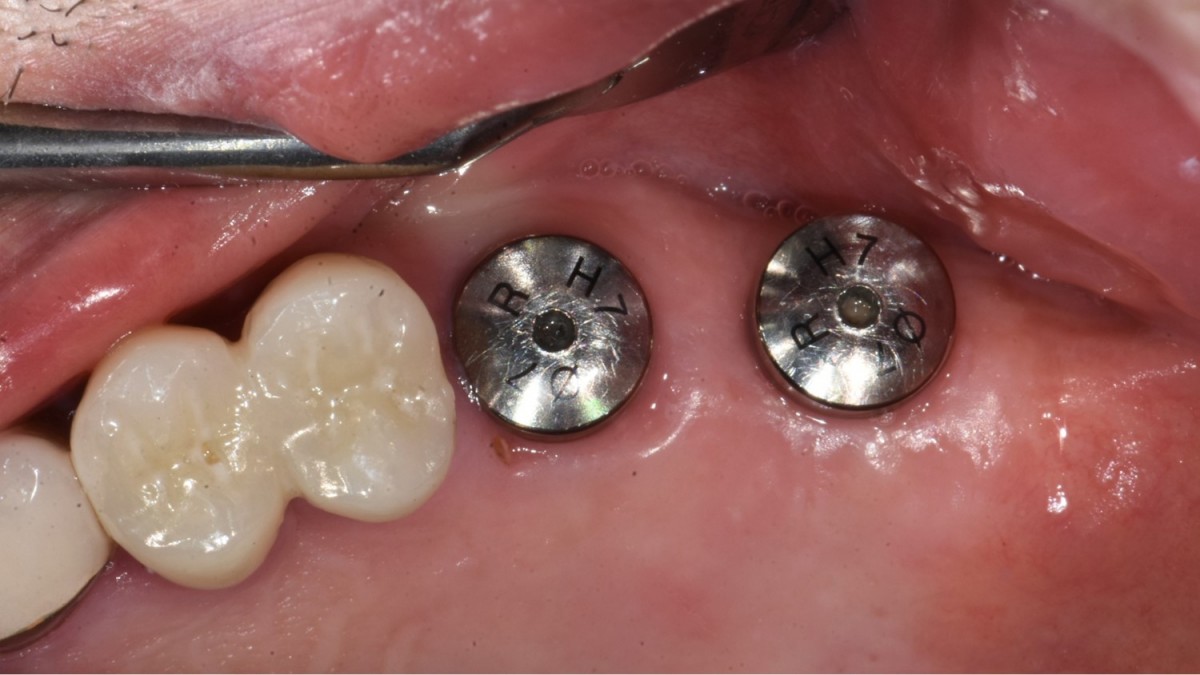

▲2 implants were placed. ArumDentistry NB1 5*10 (30Ncm) in the 1st molar and 5*10 (10Ncm) in the 2nd molar.